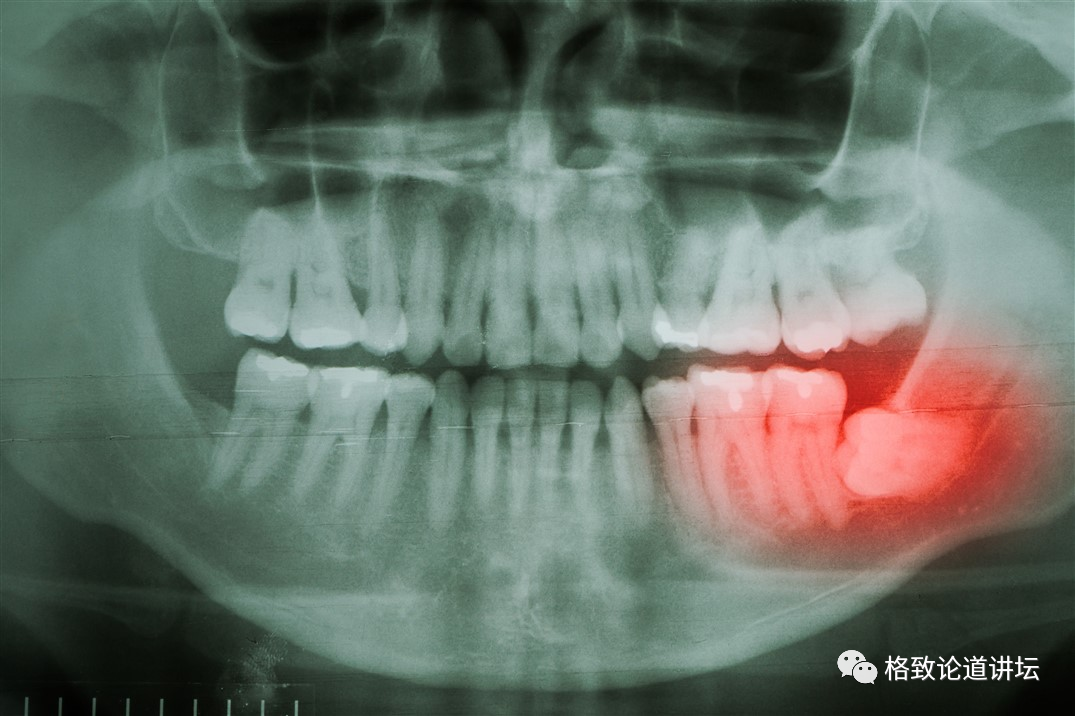

植物塑造我们的行为比我们想象的要多得多。我相信很多人到一定的岁数之后,就会有一颗特别的牙齿来捣乱:智齿。

▲ 智齿

为什么叫智齿,这跟智慧有什么关系呢?这是因为在很久以前,我们的祖先生活需要这颗牙齿,而这颗牙齿长出来的时间恰好在30岁左右,这时人已经拥有了相当多的生存智慧。而它在这个时候长了出来,所以叫智齿。但智齿明明是特别讨厌的、让我们疼痛难忍的牙齿,为什么它会有受人尊敬的、漂亮的名字呢?

因为人类祖先在生存的过程中确实依赖于这颗牙齿,或者说是依赖这一系列的牙齿。我们的祖先在非洲大草原上生存的时候,可没有今天这么好的食物。绝大多数情况下,主要的食物就是草以及树根。再好一点,就是植物的种子和果实了。植物的果实、种子还好一点,但是天天嚼草根,这很费牙,而且每天还得吃很多。

我们的近亲黑猩猩的食谱里面,大概有70%是植物性的食物;另外一位近亲大猩猩,它几乎全都是素食的,每天主要的工作就是吃,抓一把叶子往嘴里面填,不嚼碎就没办法消化得了,所以这种行为对牙齿的磨损是极大的。人类的祖先吃这些坚硬的食物,再加上不注意口腔卫生,大概到了二三十岁的时候,前面这些牙齿就全都掉光了。

这个时候想活下去,想吃东西,没有工具怎么行?智齿就是非常重要的辅助工具,让人更好地活了下去。不过在后来,人类发明了烹饪器具,可以把种子和各种各样坚硬的食材都磨碎;还发明了火,把食材变得软和又容易吸收。

▲ 人类美食带来的新问题,黑猩猩不会拔智齿

但是今天,智齿又变成了我们的负担和麻烦。大家看上图的对比就可以发现。因为吃了很多软质的食物后,人类的下颌变得越来越小。相对于猿类,人类排列牙齿的空间就非常有限了,这个时候再长出来智齿,就会产生麻烦,甚至就得去找牙医了。所以从某种意义上来讲,牙医今天的工作甚至是植物在很久以前给安排好的。